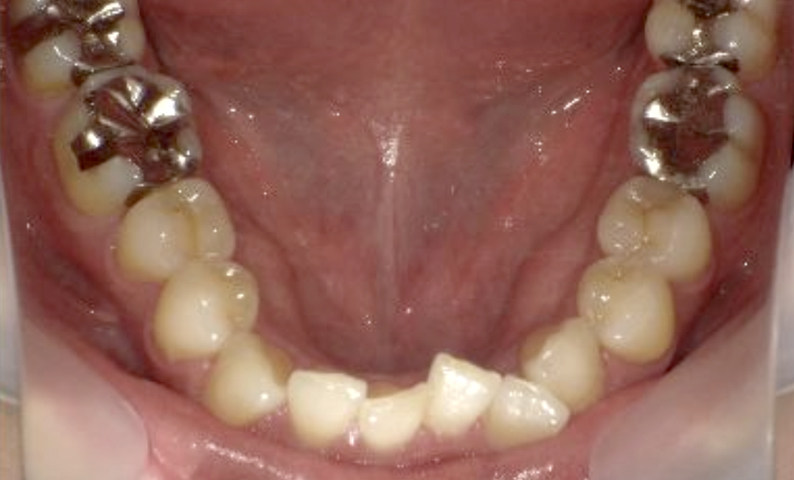

症例_003 下顎だけの部分矯正

治療期間:10ヶ月金額:24万円+税女性前歯のガタガタ下の前歯だけ上顎は補綴治療中

| Before | After |